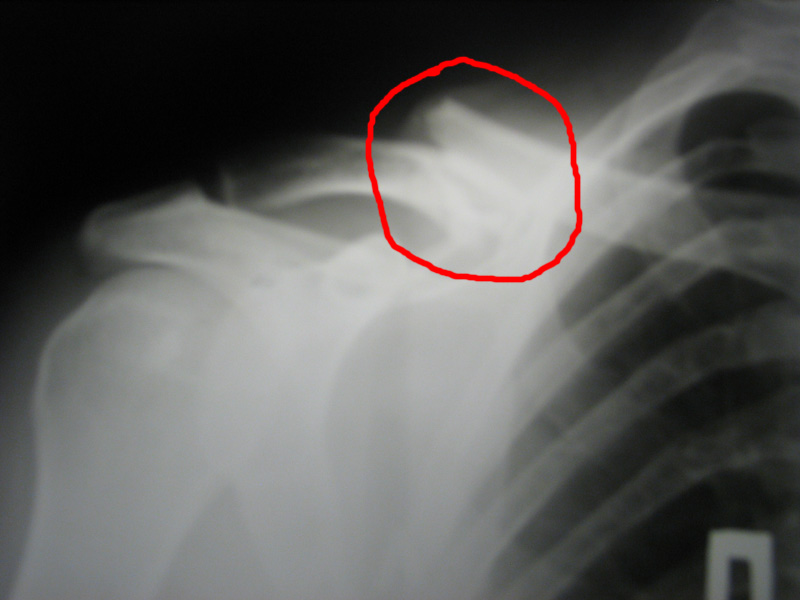

Случилось это в Сентябре прошлого года, на дёрте Олешки, в Измайловском парке. Я тогда 100% донором был, а адреналину хотелось... Ну вобщем перелетел я прилично на верблюде.

Результат - сломанная ключица, три ребра, лопатка. Самые сильные воспоминания, это как я верхушки деревьев увидел, очнулся - пот градом, дышать не могу, но ничего не болит. Хорошо друзья сомной были, довезли до больницы. Скоро лягу железочку эту выкручивать.

Нажмите на изображение для увеличения

Название: _________181.jpg

Просмотров: 610

Размер:	97.2 Кб

ID:	5295   Нажмите на изображение для увеличения

Я так понимаю на фото сломанная ключица, у тебя привезали плостину металлическую а у моего друга на снимке прямо в ключитцу вбид штыри (металлический), сочуствую неприятная штука...